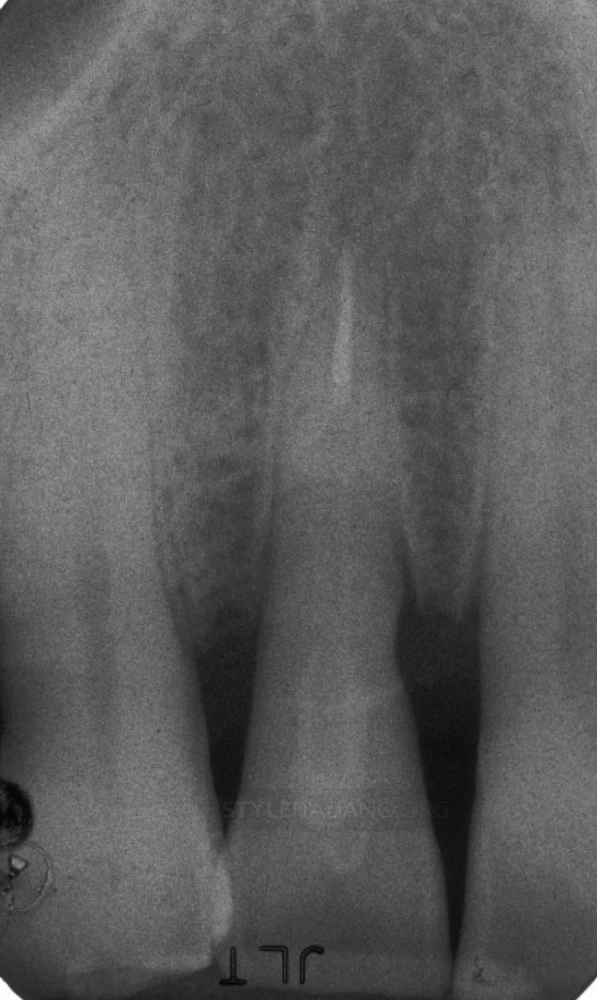

Thông qua phim X-Quang có thể thấy chân răng đã bị gãy và vị trí gãy cao hơn mào xương ổ răng, đồng thời vết gãy đã xâm nhập vào buồng bột của răng cửa bên cạnh.

Trên phim x-quang sau điều trị có thể thấy sự chắc chắn giữa gutta percha ở ống tủy, chốt sợi và đường gãy.

Khám sau khi mô mềm lành thương cho thấy lợi phục hồi tốt. Đo túi lợi không thấy bất cứ sự mất bám dính nào ở vị trí kẽ răng. Thẩm mỹ răng hoàn hảo, hài hoà trên cung răng.